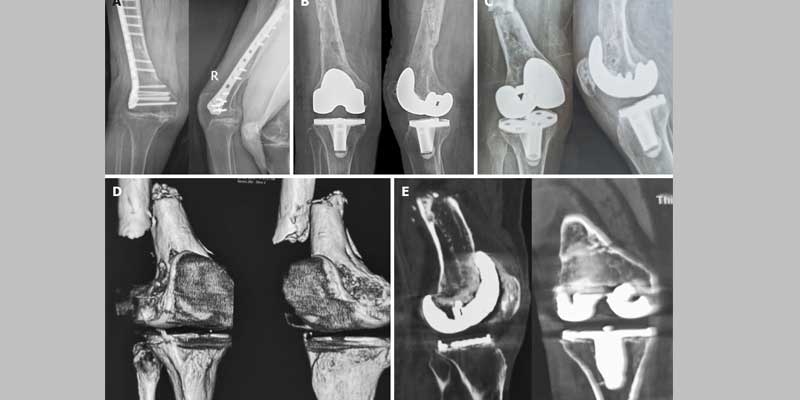

complex trauma & peri prosthetic fracture

Dr. Ramakant Bhivsan specializes in the management of Complex Trauma and Peri-Prosthetic Fractures, offering expert surgical care for challenging orthopedic injuries, including fractures around joint replacements and multiple or severely displaced bone fractures. With extensive experience in trauma reconstruction and revision surgeries, Dr. Bhivsan uses advanced fixation techniques and individualized treatment plans to restore stability, alignment, and function. His comprehensive approach includes accurate diagnosis, meticulous surgical execution, and coordinated post-operative rehabilitation. Committed to delivering the highest standard of care, Dr. Bhivsan helps patients recover from complex injuries and return to their daily lives with improved strength and mobility.